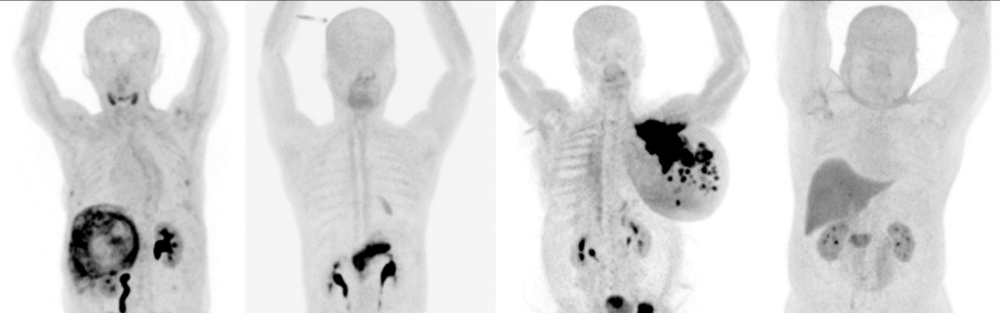

The technique is based on injecting the patient with the radiopharmaceutical FAPI intravenously, which targets fibroblast activation protein, prevalent in cancer-associated fibroblasts, after which the patient is imaged in the PET/CT. This allows for more precise imaging of various tumours. In addition, FAPI PET/CT has promising applications in identifying fibrotic diseases, such as cardiac fibrosis and chronic inflammatory conditions, which expands its diagnostic applications.

“In oncology, FAPI PET/CT has the potential to offer detailed insights into tumour biology, enhancing the accuracy of cancer diagnosis and staging. It improves the detection of cancerous tissues and plays a crucial role in treatment planning and opening the gate for future theranostics applications," Dr Khulood explained.